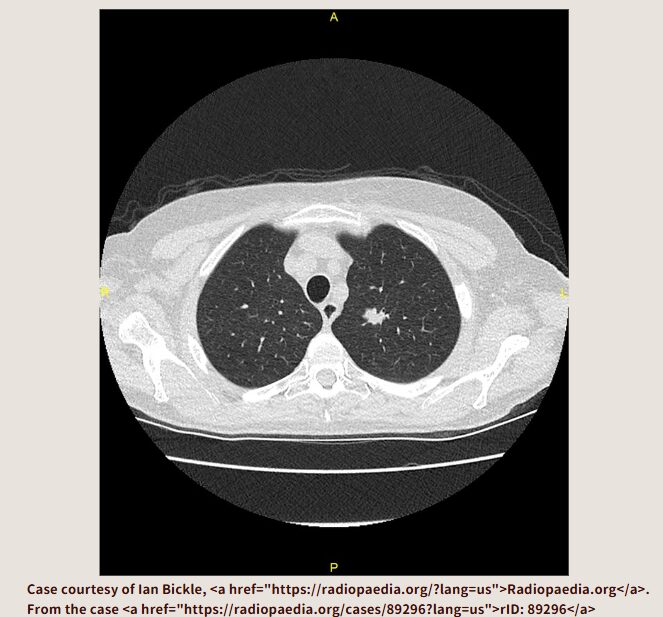

レントゲンの段階では見落としも多く、結局CTを撮ることで確定するケースがほとんどです。

初診時に呼吸器内科が不在でも、内科でCTをオーダーし、一次評価を行えば対応可能。レントゲンのみで判断するのは限界がある。

結局CT撮るんですよ。呼吸器内科の先生だって結局CT撮るんですよ。だったら、今日内科でCT撮ったほうがいいでしょう。何もなければ今日で終了です。あやしい影があったら、読影に出して(呼吸器内科の先生も読影があったほうがうれしいでしょう)呼吸器内科外来を予約してあげましょう。